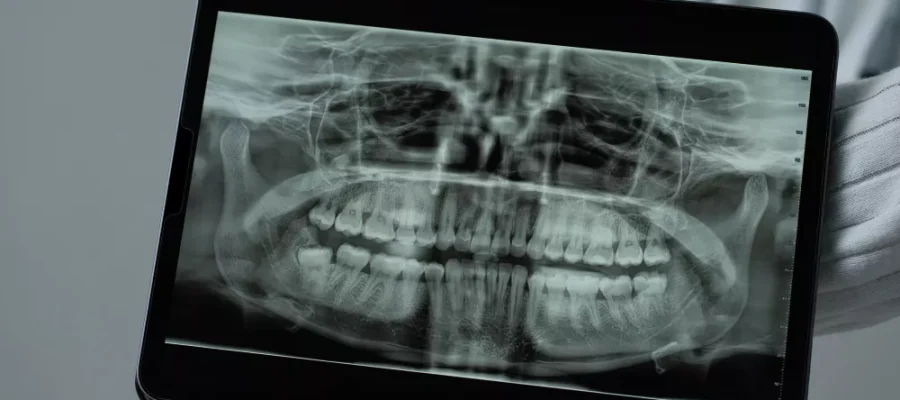

Diş hekimlerinin muayene öncesi istedikleri panoramik röntgen; dişleri, üst ve alt çeneleri, çevreleyen yapıları ve dokuları içeren tek bir görüntüde tüm ağzı görüntüleyen bir radyolojik incelemedir. Bu görüntü ile kemiklerin ve dişlerin görüntüsü sağlanır. Teknolojik cihazlar ile panoramik ve sefalometrik Röntgen incelemeleri Sonomed’de güvenli bir şekilde yapılmaktadır.

Günlük uygulamada diş hekimleri ve ağız cerrahları tarafından sıklıkla yapılan inceleme ve önemli bir tanı aracıdır. Maksiller sinüsler, diş yerleşimi ve diğer kemik anormallikleri hakkında kıymetli bilgiler verir.